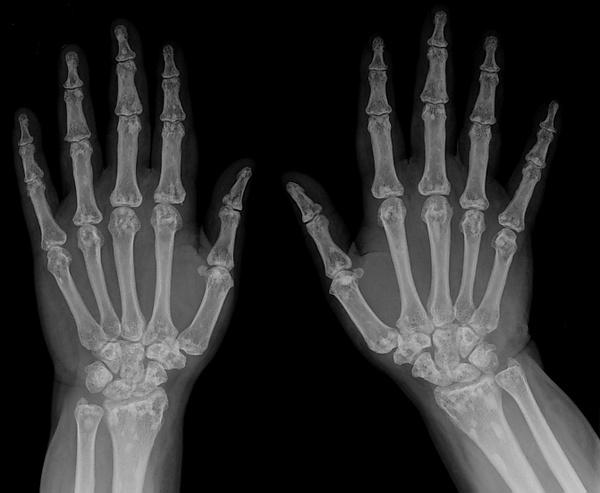

Рентгенологически на фоне почти нормальной кости в губчатом веществе эпифизов и метафизов длинных трубчатых костей, плюсневых и пястных костей, фаланг наблюдаются пятнистые очаги затемнения. Реже поражаются позвонки, рёбра, грудина, череп. Иногда заболевание сочетается с синдромом синих склер, несовершенным костеобразованием, дебильностью, эпилепсией.